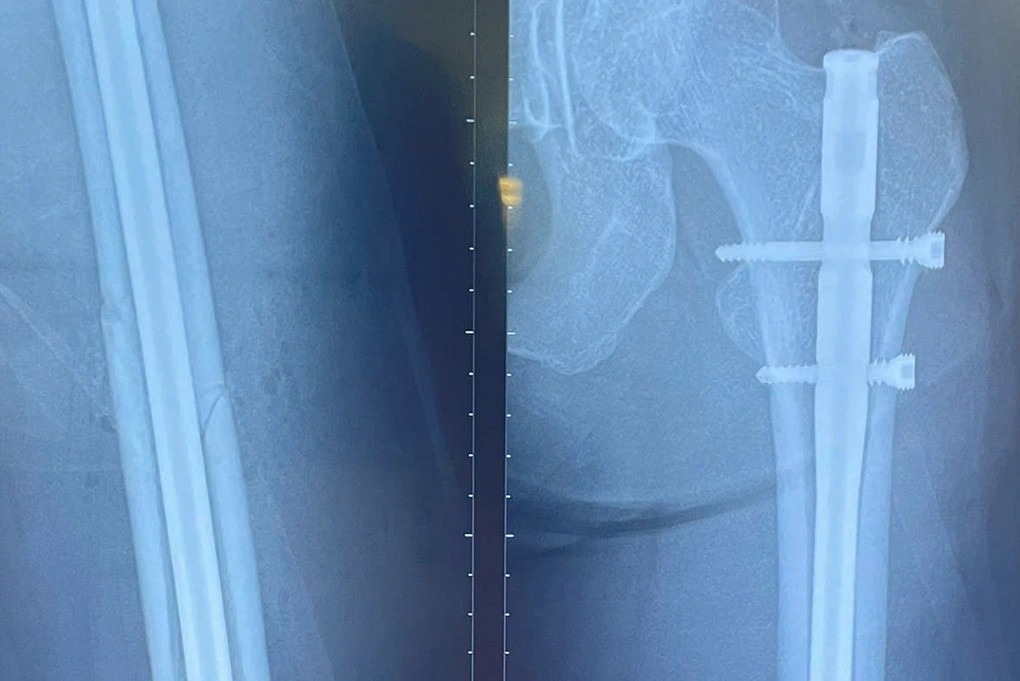

Nữ người mẫu 30 tuổi bất ngờ gặp tai nạn găy xương đùi trên sân chơi pickleball tại TPHCM. Với chiều cao 1m78, đường găy tét dọc xuống theo xương đùi trái nên ca mổ khó khăn hơn.

Bệnh nhân bị tai nạn tại một sân pickleball ở TPHCM và nhập viện để phẫu thuật cấp cứu trong t́nh trạng tổn thương đùi trái và kết quả chụp X-quang găy 1/3 giữa thân xương đùi.

Theo bác sĩ Thắng, bệnh nhân cao đến 1m78, đường găy xương tét dọc xuống theo xương đùi trái, nhiều đường chồng lên nhau nên ca mổ khó khăn hơn. Bác sĩ phải thực hiện đường mổ nhỏ, tránh ảnh hưởng thẩm mỹ cho người bệnh, nhưng phải đảm bảo đủ nắn chỉnh cố định để chống chân đi được sau một ngày phẫu thuật.

H́nh ảnh găy xương đùi của nữ người mẫu trên phim chụp. Ảnh: BVCC.

Trước ca phẫu thuật, các bác sĩ phải cân nhắc rất kỹ về vấn đề lựa chọn dụng cụ kết hợp xương và phải tư vấn, giải thích cho người bệnh về chế độ tập luyện, phục hồi. Ca mổ thực hiện lúc 14h ngày 4/4, bằng kỹ thuật đường mổ nhỏ đóng đinh với chốt 2 đầu xương đùi (đóng đinh chốt đùi). Hiện tại, sức khỏe bệnh nhân đang dần ổn định.